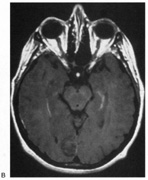

OPTIC TRACTS The optic tract is the continuation of the anterior visual system from the optic chiasm to the LGN. Only the contralateral hemifield is represented. The decussated nasal retinal fibers are not initially well aligned topographically with the other eye's temporal retinal fibers, but retinal correspondence improves towards the termination of the tract at the lateral geniculate nucleus (LGN). The retinotopic map is also tilted in the optic tracts, so that the macula is represented dorsally, inferior retina (superior visual field) laterally, and superior retina (inferior visual field) medially (see Chapter 4, Fig. 9).1 The magnocellular and parvocellular axons also may be segregated, with magnocellular axons more ventral.2 Both of these topographies are mirrored in the LGN. The main vascular supply of the optic tract is the anterior choroidal artery. The functional anatomy of the optic tract is reflected in several important clinical findings. First, partial lesions cause contralateral homonymous defects that can be markedly incongruous (different patterns of visual loss in the two eyes) because of the poor topographic alignment of the two retinal maps (Figs. 1 and 2).3,4 In contrast, lesions of the optic radiations cause only mild incongruity and striate lesions are highly congruous. Complete transection of the optic tract leads to congruous complete hemianopia, although this is less frequent than partial lesions. Reduced acuity with an optic tract lesion indicates bilateral tract damage or extension of the lesion to the optic chiasm or optic nerves.4,5 Second, because the axons in the optic tract originate from retinal ganglion cells, damage to the tract causes optic atrophy over time. This is present in both eyes, but because only half or less of the axons of each eye are affected, the atrophy is less severe than with most optic neuropathies. Also, the pattern of optic atrophy differs between the eyes. In the eye with temporal field loss, the axons from the nasal retina are affected. The fibers from the nasal periphery enter the nasal side of the disc, whereas those from the nasal macula enter the temporal disc in the papillomacular bundle. Atrophy is seen in these nasal and temporal wedges of the disc but the superior and inferior sectors are spared, because these contain fibers from the temporal retina. The result is “bow-tie” optic atrophy (see Fig. 1). In contrast, atrophy in the eye with nasal field loss affects the superior and inferior wedges and papillomacular bundle, but not the nasal wedge. This appears as diffuse or temporal disc pallor. Another distinctive optic disc picture occurs in the eye with temporal field loss when a mass lesion causes papilledema and compresses the optic tract. Disc swelling occurs in the superior and temporal disc but not in the atrophic bow-tie regions, creating “twin-peaks” papilledema (see Fig. 2).6,7 Third, because fibers for the pupillary reflex also travel in the optic tract, often there is a relative afferent pupillary defect (RAPD). With a significantly incongruous hemianopia, the RAPD may be in the eye with greater visual loss. With a complete tract lesion the RAPD is in the eye with temporal field loss,4,8 because the temporal hemifield is larger and there are slightly more axons from the nasal than temporal retina (ratio 53:47). The RAPD is a useful sign in optic tract hemianopia because it may be present at a time when optic atrophy has not yet developed (see Chapter 15).9 Other reported pupillary abnormalities include Wernicke's hemianopic pupil, which is an intraocular afferent pupil defect, with less pupillary constriction from light on the hemianopic hemiretina compared to light on the intact hemiretina. Wernicke's hemianopic pupil is difficult to elicit at the bedside because of intraocular light scatter,3 although it may be seen with computerized pupillometry (Fig. 3). The combination of optic atrophy, RAPD and field incongruity is important to recognize with homonymous hemifield defects, because it changes the differential diagnosis of hemianopia (Fig. 14). Most hemifield defects from lesions of striate cortex or the optic radiations result from vascular disease or other intracerebral pathology. Most optic tract lesions are compressive extrinsic masses, with a differential diagnosis similar to that for optic chiasmal lesions (see Chapter 6). In fact, patients with combined damage to the optic tracts, chiasm, and nerve are not rare.4,10–13 Pituitary adenomas, giant aneurysms of the internal carotid artery, meningiomas, and craniopharyngiomas are the chief causes of optic tract dysfunction. The investigation of choice is imaging of the parasellar region, with coronal and axial sections and contrast administration. Less common lesions include inflammatory conditions such as multiple sclerosis3,11,14,15 and sarcoidosis (see Fig. 1).16 Intrinsic optic pathway gliomas may occur in the optic tracts. Vascular lesions are rare, but there are reports of cavernous angiomata10,17 or arteriovenous malformations.18 Optic tract infarction can complicate anterior temporal lobectomy, possibly from vasospasm of the anterior choroidal artery.19 Trauma can affect the optic tract.3 Radiotherapy of pituitary tumors may be followed years later by optic tract necrosis.13 Optic tract dysfunction is a side effect of alpha-interferon.20 On occasion there is congenital absence of the optic tract 21; such patients are often unaware of their hemianopia. Associated abnormalities are unusual.3 These include endocrine disturbances from hypothalamic dysfunction and memory impairment from temporal lobe involvement,22 reflecting the proximity of the optic tracts to these structures (see Chapter 4). LATERAL GENICULATE NUCLEUS The LGN is a subnucleus in the ventro-postero-lateral corner of the thalamus. Neighboring thalamic subnuclei include the medial geniculate nucleus ventromedially, ventral posterior nucleus dorsomedially, and pulvinar superiorly and dorsally. The medial geniculate nucleus gives rise to the acoustic radiations, which pass by the dorsomedial aspect of the LGN on their way to the auditory cortex in the temporal lobe. The optic radiations arise from the dorsolateral surface of the LGN. Ventrally, the hippocampus and parahippocampal gyrus face the LGN across the ambient cistern and the inferior horn of the lateral ventricle. The LGN has a dual blood supply: the anterior choroidal artery, a branch of the internal carotid artery, and the lateral choroidal artery, a branch of the posterior cerebral artery. The anatomy of the vascular territories within the LGN has been debated. Initial studies suggested that the anterior choroidal artery supplied the medial LGN as well as the optic tract and the lateral choroidal artery the lateral LGN. However, experience with surgical arterial lesions concluded that the anterior choroidal artery supplied both the lateral and medial aspects and the lateral choroidal artery supplied the hilus and midzone of the LGN. In addition to its function as a relay in the visual pathway, the LGN is also a site of modulation, by back-projections from visual cortex23,24 and afferent projections from the brainstem reticular formation and superior colliculus.25 Some of the corticofugal input influences the stimulus selectivity of LGN neurons.24 Others postulate that these nonretinal inputs play a role in gating visual transmission through the LGN, and thus participate in selective attention.23 The LGN is a triangular shaped structure with six roughly horizontal layers containing segregated inputs from the two eyes (see Chapter 4, Fig. 8). The ventral two layers are the magnocellular layers, whereas the other four layers are the parvocellular component; these differ in many structural and functional aspects (see Chapter 4). The LGN has a retinotopic pattern that is a continuation of that found in the optic tract. The macula is represented in a dorsal wedge, including the hilum and projecting posteriorly, whereas the most peripheral fibers are located ventrally. Superior retinal fibers (contralateral inferior visual quadrant) are in the medial horn and inferior retinal fibers (contralateral superior visual quadrant) are in the lateral horn. Because the LGN is small and relatively secluded, lesions here are rare. Its intimate relation to the optic tract and optic radiation make it difficult to be certain that a visual defect results from LGN damage rather than damage to these structures. Indeed, visual field defects from purported LGN lesions resemble visual field defects from optic tract or optic radiation lesions. Three main types of hemianopic defects have been described. The first is an incongruous hemianopia, much like that seen with optic tract lesions, reflecting the continued segregation of ocular inputs in the LGN. The other two patterns are sectorial hemianopias reflecting the unusual territorial division between the anterior and lateral choroidal arterial supplies. With lateral choroidal ischemia, the hilum and middle zone of the LGN are affected, causing a wedge-shaped visual defect straddling the horizontal meridian (Fig. 4).26 With anterior choroidal ischemia, the lateral and medial tips of the LGN are infarcted, resulting in the reverse defect, loss of the superior and inferior aspects of the contralateral hemifield with sparing around the horizontal meridian.27,28 Unusual cases of presumed bilateral LGN damage have presented with an “hourglass” shape to either the visual field defect29,30 or the region of spared vision.31 Optic atrophy often accompanies LGN lesions. If there is damage to almost all of the LGN, the optic atrophy has a similar appearance to that seen with optic tract lesions. If there is partial damage causing sectorial hemianopias, then the optic atrophy may be more subtle and restricted to the relevant sectors of the disc.26,27 However, because the afferent fibers subserving the pupillary light reflex already have departed for the pretectum, there is no RAPD with lesions of the LGN. With incongruous hemianopia and optic atrophy, this is the only feature that permits distinction between optic tract and LGN lesions. A variety of pathologies have been reported with LGN lesions. Infarction is the most likely cause of sectoranopia, given the dependence of such defects on the vascular anatomy,26,27 but astrocytomas and arteriovenous malformations are also reported. Furthermore, the LGN appears to be a target of central pontine myelinolysis, a syndrome associated with excessively rapid correction of hyponatremia.29,30,32 LGN damage rarely is a parainfectious complication of traveler's diarrhea.31 OPTIC RADIATIONS The optic radiation may be affected anywhere in its course (see Chapter 4); the type of visual field defect reflects the site of damage. Ischemic or hemorrhagic lesions of the internal capsule affect the optic radiation while it is still a relatively compact bundle, usually causing a complete homonymous hemianopia. A similar defect can arise from damage close to the termination in striate cortex (Fig. 5). Lesions of the ventral fibers in the anterior temporal lobe cause a contralateral superior visual quadrant defect (Fig. 6). Most often this defect aligns on the vertical meridian, with variable extension toward the horizontal meridian and central vision.33 Lesions of the dorsal fibers in the parietal lobe cause an inferior visual quadrant defect (Fig. 7). Because there is no sharp demarcation of the dorsal fibers from the ventral fibers in this portion of the posterior pathway, the defect seldom aligns along the horizontal meridian.33 Overall, quadrantanopia is more frequent with lesions of striate cortex.33 Lesions of the temporal lobe more than 8 cm posterior to its anterior tip can affect both upper and lower radiations. Small lesions also may affect certain portions of the radiations and spare others; for example, damage to the midportion of the optic radiation can mimic the sectoranopias of LGN lesions (Fig. 8).34 Although there can be some incongruity to the visual field defects of optic radiation lesions, this is less marked than the incongruity with optic tract lesions. Unlike lesions of the retino-geniculate pathway or LGN, lesions of the geniculostriate axons do not lead to optic atrophy (with the exception of some congenital lesions, through trans-synaptic degeneration) or pupillary defects. However, frequently there are other signs of cerebral damage,33 especially if the lesion is large. Thus, temporal lobe lesions cause superior quadrantic defects and sometimes also complex partial seizures, auditory or complex visual hallucinations (some of which may be seizures), memory problems, or a Wernicke's aphasia if the dominant hemisphere is involved. Parietal lesions with mainly inferior quadrantic defects may cause cortical sensory disturbances, such as impaired two-point discrimination and graphesthesia, and impaired smooth pursuit toward the side of the lesion. With dominant hemisphere lesions, Gerstmann's syndrome (acalculia, finger anomia, right-left disorientation, and agraphia) may occur, as may a variety of aphasic syndromes, including alexia with or without agraphia, Wernicke's aphasia, or global aphasia. The differential diagnosis of optic radiation lesions reflects the variety of cerebral hemispheric pathologies. Unlike lesions of the optic tract, most are infarcts in the posterior cerebral or middle cerebral artery territories. Tumors, vascular malformations, infections, and leukodystrophies are also possibilities. The temporal profile of the illness often is the major clue to the etiology. STRIATE CORTEX The primary visual area in the medial occipital lobe goes by several names: Brodmann's area 17, “visual area 1” or V1, “calcarine cortex,” and “striate cortex” (see Chapter 4). The exact position of striate cortex varies among individuals. Although the parieto-occipital fissure forms a reasonably reliable anterior dorsal boundary, the posterior limit containing the macular representation is more variable, extending from the medial occipital surface over the first one or two centimeters of the posterior surface of the occipital lobe (see Chapter 4, Fig. 10). The main vascular supply of striate cortex derives from the posterior cerebral artery (see Chapter 4, Fig. 15). A parieto-occipital branch supplies the superior calcarine bank, a posterior temporal branch supplies its inferior bank, and a calcarine branch supplies the central region posteriorly; however, individual variation exists.35 Perhaps most importantly, the occipital pole is at the junction (watershed zone) of the vascular territories of the posterior and middle cerebral arteries, and again there is marked variation as to which artery supplies the foveal representation in striate cortex.35 The retinotopic arrangement in striate cortex is well known (see Chapter 4), and confirmed with recent imaging studies of lesions.36 The foveal representation is posterior, at the occipital pole, and the far peripheral field is anterior, on the medial occipital surface.37,38 The superior bank of the calcarine fissure receives input from the inferior visual field, whereas the inferior bank contains the representation of the superior visual field. The most anterior part of striate cortex represents the monocular temporal crescent, the region of temporal field in the contralateral eye that lies beyond the limits of the nasal field (60°) of the ipsilateral eye. As in most of the visual system, there are fewer neurons devoted to peripheral vision than to central vision: Over half of striate cortex is devoted to the central 10° (cortical magnification).36,39 Occipital cortex contains a mixture of monocular and binocular cells arranged in ocular dominance columns, but large separations between the inputs of the two eyes are not present. Visual Field Defects from Striate Lesions Focal destruction of striate cortex produces a homonymous contralateral visual hemifield defect. Unlike the scotomata from lesions of the optic radiations and especially the optic tracts, the hemianopic defects from striate lesions are highly congruent, with virtually identical defects in the two eyes. Complete destruction of striate cortex causes complete visual loss in the contralateral visual hemifield. Because this involves not only peripheral vision but also the contralateral half of the foveal region it is called a macula-splitting homonymous hemianopia. This may occur with posterior cerebral artery ischemia in a patient whose entire striate cortex is supplied by that artery. Macula-splitting hemianopias can occur with complete lesions anywhere along the retrochiasmal visual pathways, and thus lack localizing value (see Fig. 5). Other signs may help in localization. Reading is particularly impaired by involvement of the central 5°.40 Partial lesions of the striate cortex are frequent. With posterior cerebral infarcts, a macula-sparing hemianopia occurs in patients with adequate collateral circulation of the macula region (occipital pole) from the middle cerebral artery (Fig. 9).35 Previously, macula-sparing was thought to result from bilateral representation of a small stripe flanking the vertical meridian, which expanded to as much as 3° at the fovea.41 However, studies of monkey V1 do not find bilateral representation of the hemimaculae,42 and computed tomography (CT) and magnetic resonance imaging (MRI) studies in humans with hemianopia document the correlation of macular sparing with sparing of the occipital pole.43,44 Also, careful perimetry of hemianopes with the scanning laser ophthalmoscope shows that, although there is a slight overlap from the seeing field into the blind field along the meridian, macular sparing of 2° to 5° is only present in some patients.45,46 Therefore sparing more likely reflects the extent of occipital pathology than retinal anatomy. Macula-sparing has some localizing value, because it is seen mainly with lesions of striate cortex. The upper and lower banks can also be involved separately. Ischemia can do this because the banks have separate blood supplies. Upper bank infarcts cause homonymous contralateral inferior quadrantanopia (Fig. 10) and lower bank infarcts cause superior quadrantanopia. Although altitudinal defects have been reported occasionally,47,48 most quadrantic defects do not align at the horizontal meridian, because the upper field merges without interruption into the lower field in the depths of the calcarine fissure. Thus it has been argued that quadrantic defects that respect the horizontal meridian are caused by involvement of area V2, surrounding striate cortex,49 which remains controversial. Quadrantanopias are three times more common with striate lesions than with optic radiation lesions.33 Striate quadrantanopias are more frequently isolated signs but can be associated with other signs of higher cortical visual dysfunction, such as pure alexia or hemiachromatopsia, whereas optic radiation quadrantanopias usually are accompanied by hemiparesis, dysphasia, or amnestic problems.33 Selective lesions can also occur along the anterior-posterior extent of striate cortex. A lesion of the occipital pole alone causes homonymous central hemiscotomata (Fig. 11).44,50 This can occur with watershed infarcts during systemic hypoperfusion. Slightly more anterior lesions in the middle zone of striate cortex cause homonymous peripheral scotomata (Fig. 12). The highly congruent, homonymous nature of these defects and their restriction to one hemifield differentiate these from ocular causes of central or paracentral visual loss. Lesions with such small field defects can be missed on CT.43 MRI with coronal sections through the occipital lobes should be performed, although even this may miss small lesions, particularly at the occipital pole. A near-complete lesion that spares only the most anterior portion of V1 causes a nearly pathognomonic field defect, hemianopia with sparing of the monocular temporal crescent (Fig. 13). The hemianopia involves the whole nasal hemifield of the ipsilateral eye but the temporal hemianopia of the contralateral eye spares a crescent-shaped island of vision in the far periphery.51 This is the monocular temporal crescent, the region of the visual field that is represented in the temporal field of one eye but not the nasal field of the other. The initial sense of incongruity may raise suspicions of an optic tract lesion; however, the absence of optic atrophy and RAPD, the high congruity of the homonymous defect inside 60°, and the location of the crescent outside 60° eccentricity, indicate that the lesion must be in striate cortex. The converse defect, a monocular temporal crescentic scotoma, can occur with a retrosplenial lesion, along the parieto-occipital sulcus.52 Most striate lesions are infarction, mainly from posterior cerebral artery occlusion (Fig. 14), with sudden onset visual loss and sometimes headache.53 In about half, the visual field defect is the only deficit,53 but in others damage to medial occipito-temporal regions causes amnesia, prosopagnosia, and color perception defects. A syndrome of agitated delirium and hemianopia occurs with lesions of the medial occipital lobe, parahippocampus, and hippocampus.54–56 Brainstem signs include impaired level of consciousness, III nerve palsy, dysarthria and hemiplegia.53 Causes of ischemia are most frequently cardiac emboli and vertebrobasilar occlusive disease; migraine is a rare cause of permanent defects.53 Hemorrhage, vascular malformations, primary and secondary malignancies are much less common.33 Bilateral lesions of striate cortex are not rare. Focal midline lesions such as tumors or traumatic injury may affect both striate cortices concurrently, because the right and left striate cortices face each other on the medial occipital surface. The most common cause, however, is posterior circulation ischemia.57 This can affect both striate cortices either simultaneously or sequentially,57 because the right and left posterior cerebral arteries have a common origin from the basilar artery. Twenty-two percent of patients with a unilateral occipital infarction develop bilateral infarction over 3 years.58 Bilateral incomplete hemianopia is distinguished from bilateral optic nerve or ocular disease by the high congruity of the visual fields and step defects along the vertical meridian which indicate the hemifield nature of the visual loss (Fig. 15).57 Such steps are important to seek with a skilled perimetrist, but even so they can be difficult to demonstrate with bilateral hemiscotomata from occipital pole lesions.59 Bilateral quadrantanopias can occur,47,48 often in patients with prosopagnosia and achromatopsia for example, and may mimic the altitudinal defects of optic neuropathy. Cerebral Blindness Cortical blindness is a loosely used term, at times referring to visual loss from occipital lobe damage, even if the loss is incomplete. Hence hemianopia or bilateral quadrantanopia has been called cortical blindness. It is best reserved for bilateral complete or severe hemianopia, with acuity at light perception only or worse, and no detectable peripheral vision. Because lesions may involve both gray and white matter, cerebral blindness is a better term. Cerebral blindness can be persistent or transient. The most frequent cause of persistent cerebral blindness is cerebrovascular infarction.60 In addition to the common causes of emboli or atherosclerosis, it has been reported with vertebrobasilar arteritis,61 subclavian steal,62,63 and hypotension from antihypertensive medication.64,65 Cerebral blindness can complicate cardiac surgery, through hypotension or emboli.60 A rare vascular cause is rupture of occipital mycotic aneurysms with endocarditis.66 Cerebral blindness is distinguished from ocular disease by both normal pupillary light responses and normal fundoscopic examination. These may lead to an erroneous diagnosis of factitious visual loss. Associated signs of damage to parietal or temporal structures help to confirm cerebral blindness but may not always be present. Visual evoked potentials are of limited diagnostic value. They can be altered voluntarily by subjects without visual loss67 and can be normal in patients with striate lesions.68,69 They cannot differentiate between blind and seeing children with neurologic disease,70 and normal or abnormal results do not predict visual outcome.60,71 Absent evoked responses are rare and may only occur early in the course.70 Absent alpha rhythm on electroencephalography72,73 is reportedly a more sensitive diagnostic sign than abnormal visual evoked potentials.60 CT scans can be normal, but modern MR imaging with coronal images through the occipital lobe should reveal most striate or optic radiation lesions with complete and persistent visual loss (Fig. 16). Single photon emission computed tomography (SPECT) scans may reveal bilateral functional defects in cases with unilateral MRI lesions.74